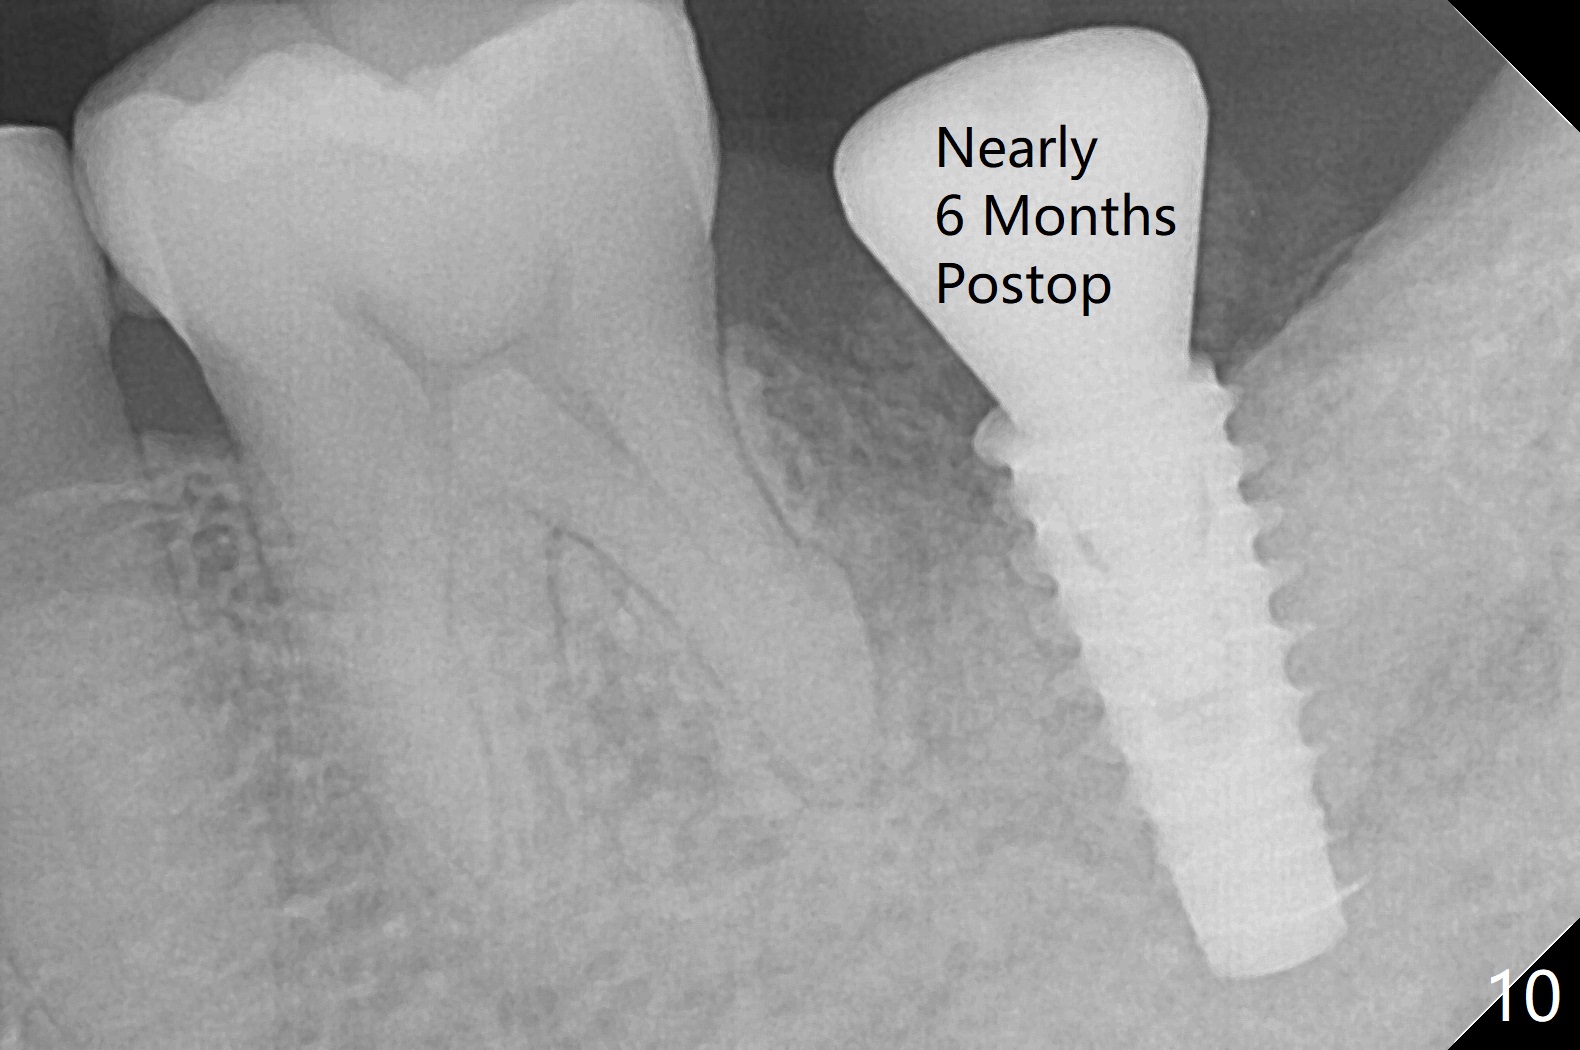

After placement of a 5x11 mm implant and cover screw at #18, allograft mixed with PRF (sticky bone) is placed in the peri-implant space, but it appears that bone density in the apical region (Fig.1 A) is lower than that in the coronal one (C) because of a constriction between the implant and the distal crest (*). Ideally the undercuts (Fig.2 *) of the extraction socket (black area) should be identified. Place bone graft in the undercuts (Fig.3 red circles) after osteotomy (white outlines) and before implant placement! A 4.5x1 mm temporary abutment is placed for an immediate provisional. The 2nd shortcoming of this case is that the implant is placed a little buccal. The papilla mesial to the immediate provisional (Fig.4 P) looks normal 4 days postop (no food impaction is expected when a final restoration is cemented). Additional acrylic (*) was placed to close a buccal gap when the provisional was seated with the temporary abutment. The patient reports loss of a piece of material in 4 days. It must be the additional acrylic, since it is absent 6 weeks postop (Fig.5). The provisional (Fig.5 P) looks wide, probably related to post-extraction gingiva and bone atrophy (Fig.6, 7 *). Bone graft (Fig.6 <) becomes a component of the gingival cuff. The provisional is re-trimmed for better oral hygiene. The gingival cuff is basically healthy 3.5 months postop, although the temporary abutment is loose and the implant is tender to rewinding and winding (Fig.8). The implant seems to remain non-osteointegrated 3.5 months postop (Fig.9). Although the bone density around the implant increases nearly 6 months postop (Fig.10), the implant remains tender when a 5x4(4) mm pair abutment is tightened. The healing abutment is reused. The bone density around the implant increases 11 months postop (Fig.11). Uncover is done with 5.5 mm profile drill. One month post uncover (12 months postop), the implant remains unstable (Fig.12). Prepare sticky bone x1. Make incision for exploration, including retightening the implant after Titanium brush and H2O2 Q-tip rubbing. If needed, a larger and shorter UF implant is a replacement (Fig.13). The implant is removed, cleaned with Titanium brushes and H2O2 in vitro and repositioned 12 months postop (Fig.14: arrow (gaps: post granulation tissue removal)). The gaps are regrafted with sticky bone and covered with PRF membrane and Cytoplast. Although the patient complains of severe pain the first 2-3 postop, the wound is apparently healing 12 days postop. The Cytoplast is exposed asymptomatic 5 weeks postop (Fig.16) and removed (Fig.17). The wound appears to have healed without loss of the bone graft (Fig.18).术后四个月伤口愈合,骨粉几乎没有丢失,有骨小梁形态(图十九:*)。切开,刮匙去骨,有一定硬度,即刻放置修复基台,完全就位(图二十),制备临时牙冠,牙周敷料固定组织瓣(没有缝线)。